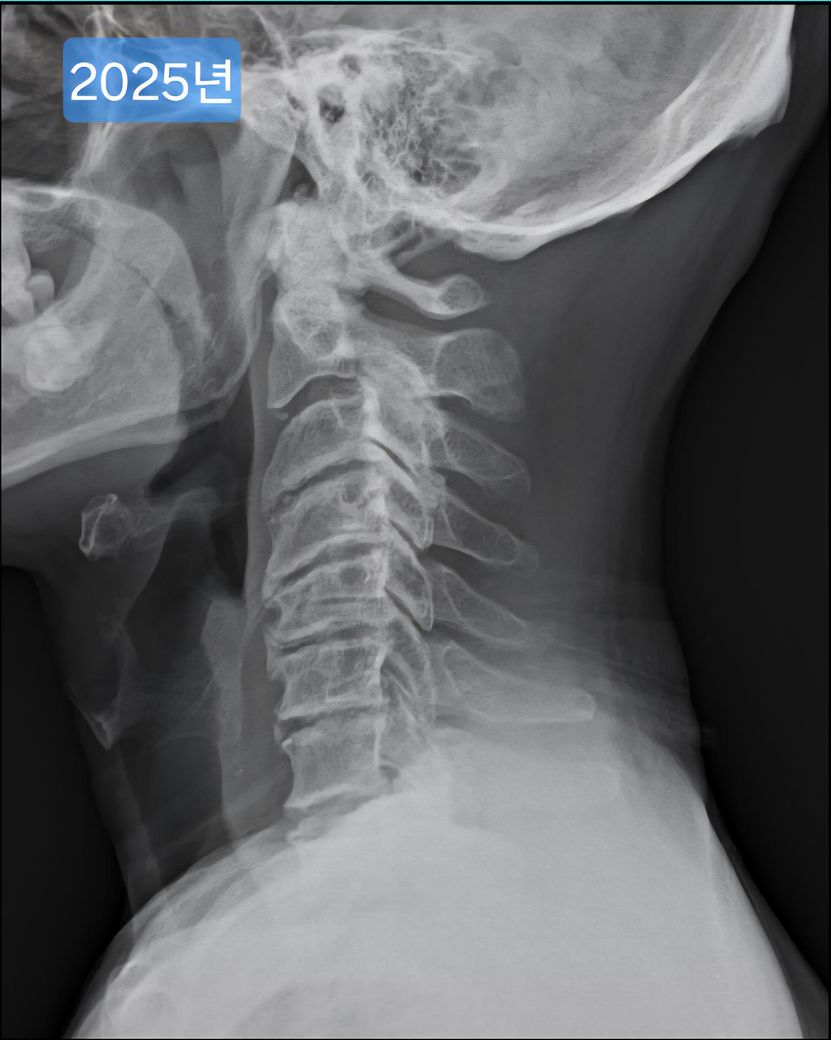

목 엑스레이 사진입니다. 많이 심각한걸까요?

오늘 찍은 2025년도 엑스레이와 9년전 사진을 업로드 해 드리겠습니다.

(이미지에 좌측상단에 해당연도 표시했습니다.)

1. 2016년과 2025년도 목이 상태가 많이 변했나요?

제가 보기엔 9년전에도 경추사이 간격이나 일자목이나 비슷한듯 보여서요.

->우선 사진상으로 봤을 땐 과거에도 충분히 경추 사이의 간격이 좁고, 목의 커브는 C자의 만곡 보단 일자목과 비슷해보이며 시간이 지나면서 누구나 겪는 퇴행성의 과정으로 보여집니다.

1. 눈에띄게 큰 변화는 아니지만 어느정도 변화는 있습니다.

9년 전과 비교했을 때 경추 간격과 일자목 형태가 크게 달라진 것 같지 않아 상태가 오래 유지 된 것으로 보입니다. 오랫동안 비슷한 형태라면 큰 통증이나 신경 증상이 없다면 생활에 지장을 주지 않는 범위일 수 있습니다.